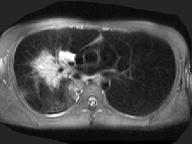

问题 男,28岁,咳嗽,咯血,消瘦盗汗1个月余,影像学检查如图。最可能的诊断为 ( )

选项 A.类风湿肺炎 B.右上肺周围型肺癌 C.右上肺浸润型肺结核 D.右上肺炎性假瘤 E.右上肺曲真菌感染

答案 C